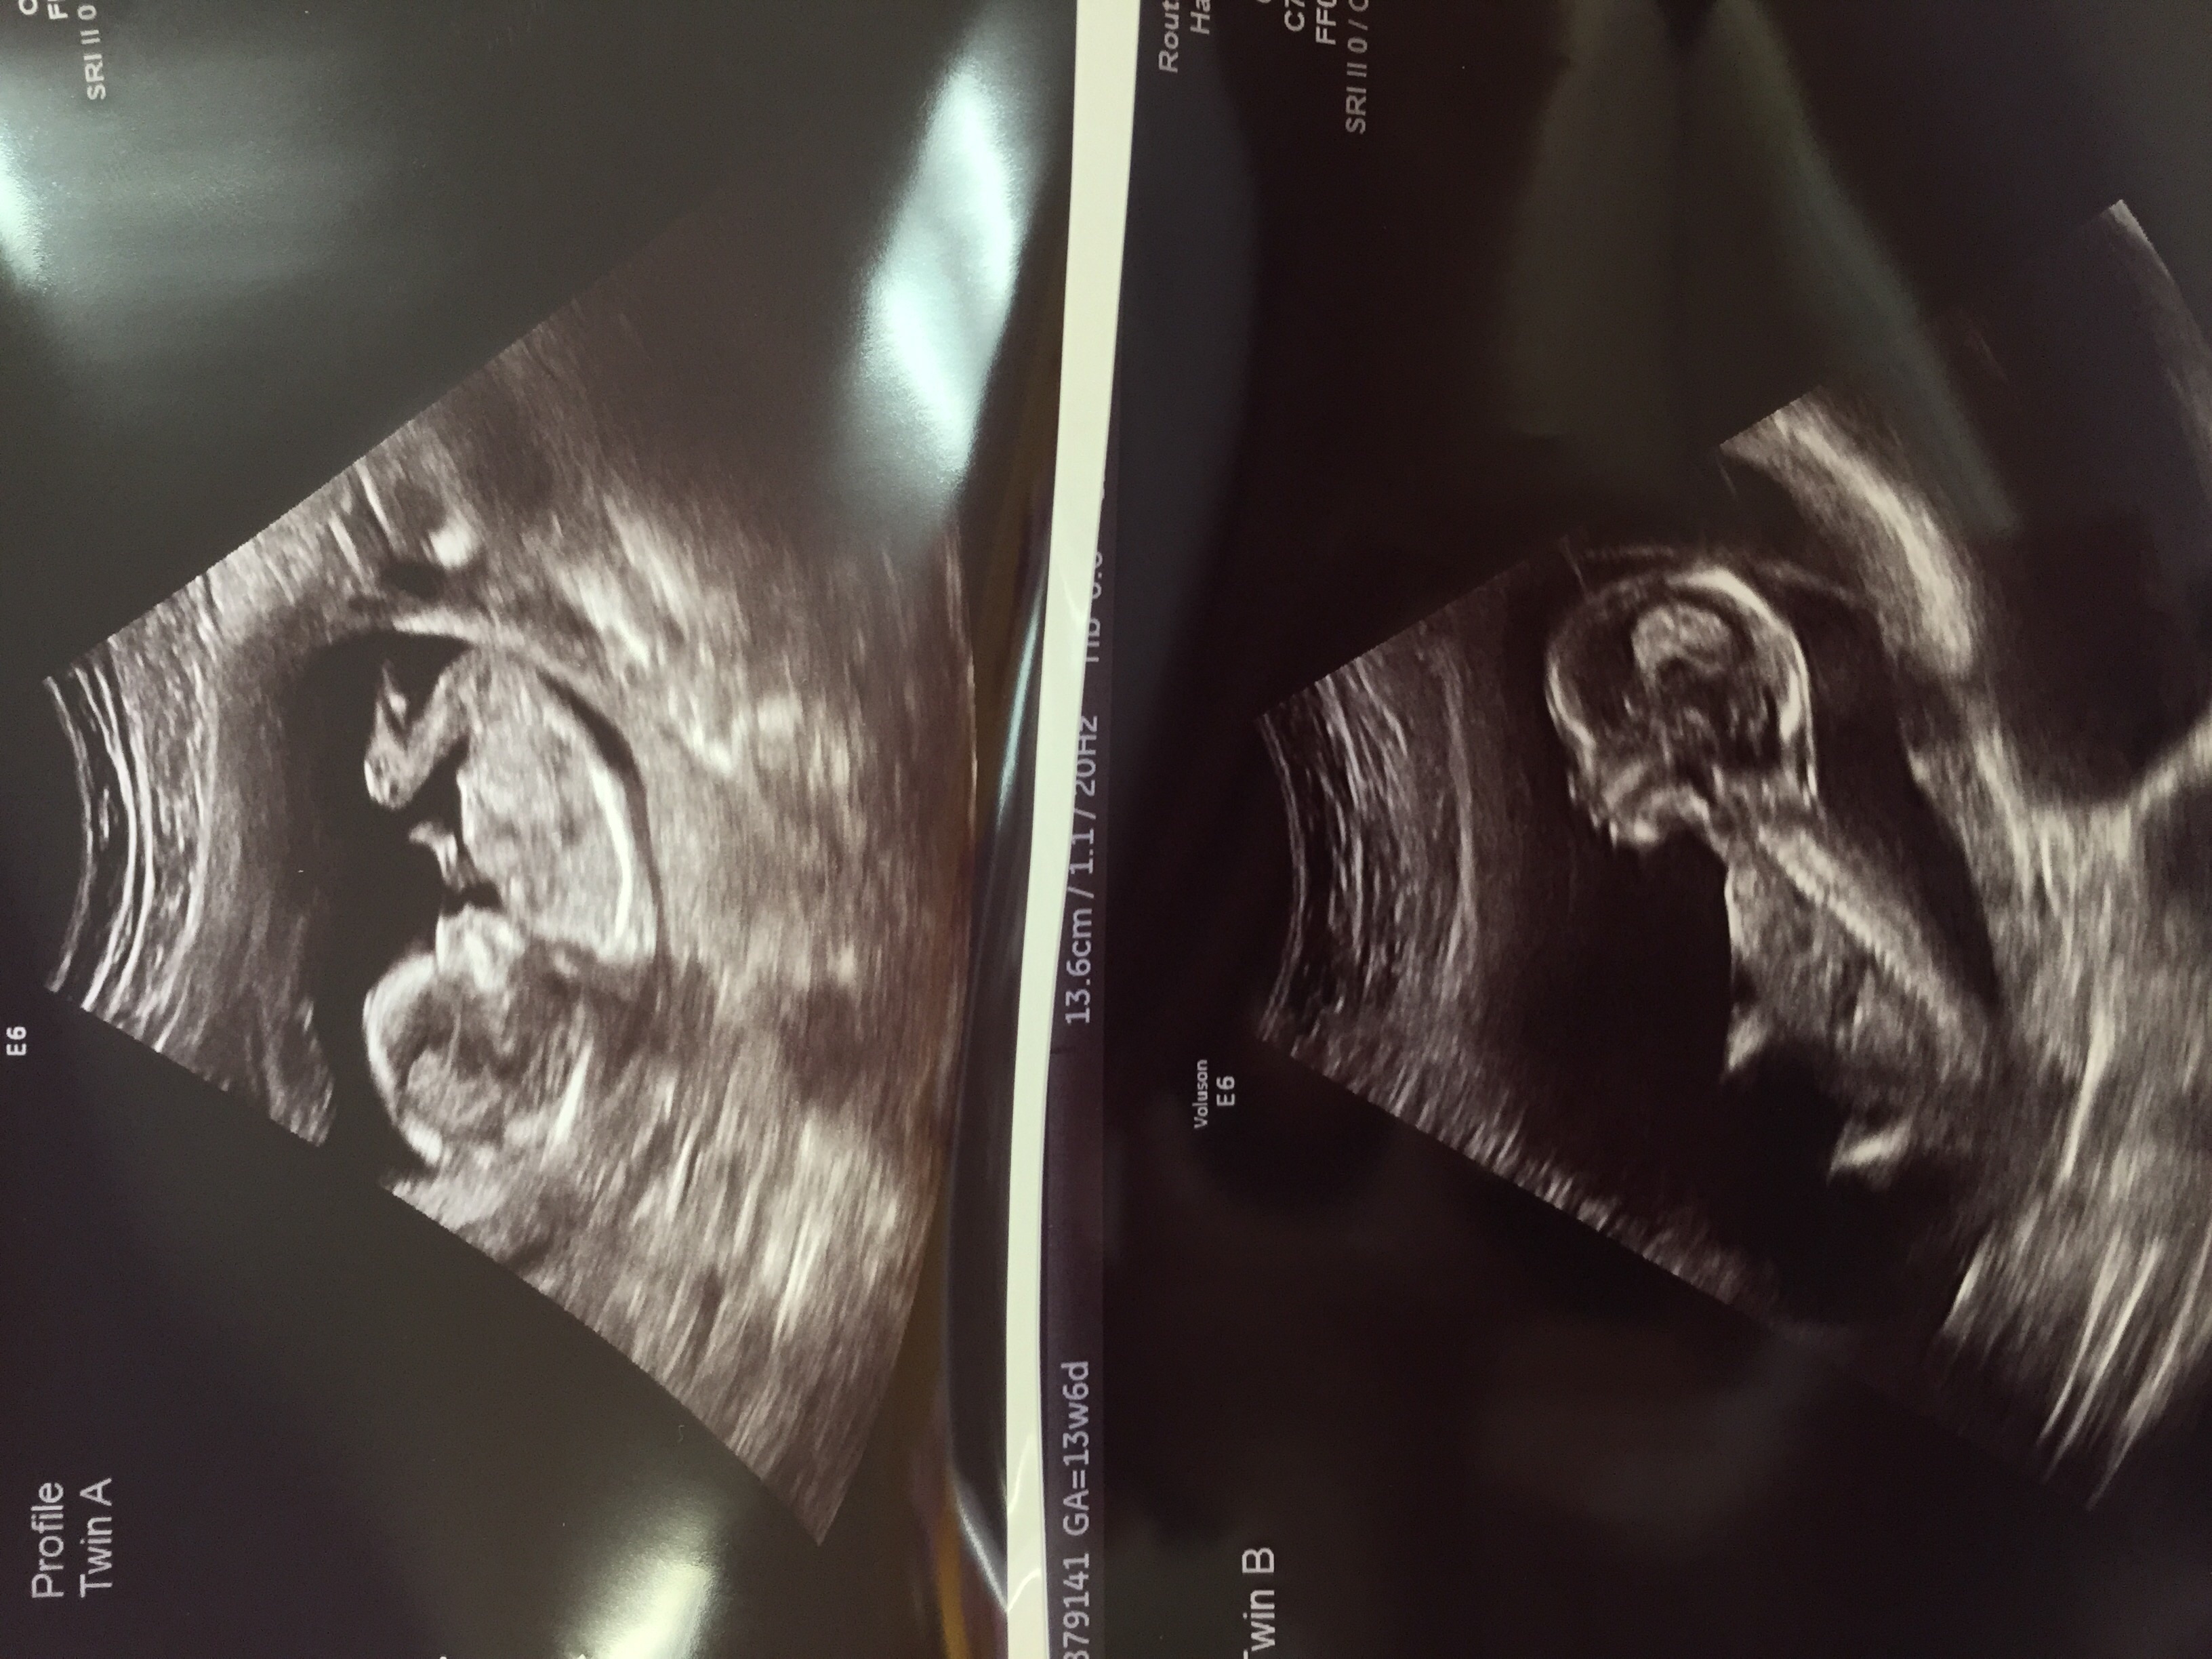

Our little bub at 12+3. What a jumping bean! I was so surprised by how much movement we observed that I couldn't stop laughing. Must be an exhausting life in there!

Had our second ultrasound baby was super active and was sucking its thumb ! Heartbeat was 156 Bpm.Ultrasound taken at 12 wks 4 days and today I'm 13 weeks ! Does anyone have a gender guess for my little nugget ? ❤️